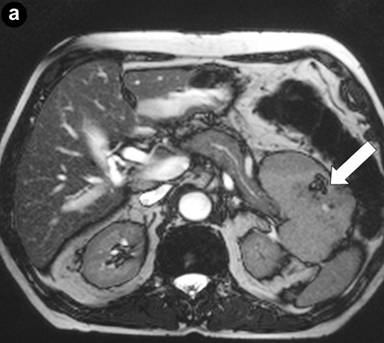

Postoperative histological examination of the resected specimen or taken biopsies revealed pancreatic metastases of extrapancreatic malignomas (Figure 1) in 8 patients (renal cell carcinoma, n=3; melanoma, n=2; duodenal gastrinoma, n=1; breast cancer, n=1; retroperitoneal liposarcoma, n=1). In 10 patients (52.6%) the following rare benign tumors were detected: solid pseudopapillary tumor of the pancreas (n=3) (Figure 2), mature teratoma of the pancreas (n=2) (Figure 3), capillary hemangioma of the pancreas (n=1) (Figure 4), intrapancreatic accessory spleen (n=1) (Figure 5), lymphoepithelial cyst of the pancreas (n=1) (Figure 6), hamartoma of the pancreas (n=1) (Figure 7), and pancreatic sarcoidosis (n=1). In one patient an advanced yolk sac tumor of the pancreas with peritoneal carcinosis was diagnosed (Table 2).

Figure 1. Intrapancreatic metastasis of a renal cell carcinoma (arrow). a. Preoperative CT scan. b. Histology of a pancreatic metastasis of a renal clear cell carcinoma (G2); tumor cell clusters (arrow), pancreatic parenchyma with chronic inflammation on the right (H&E-staining). |